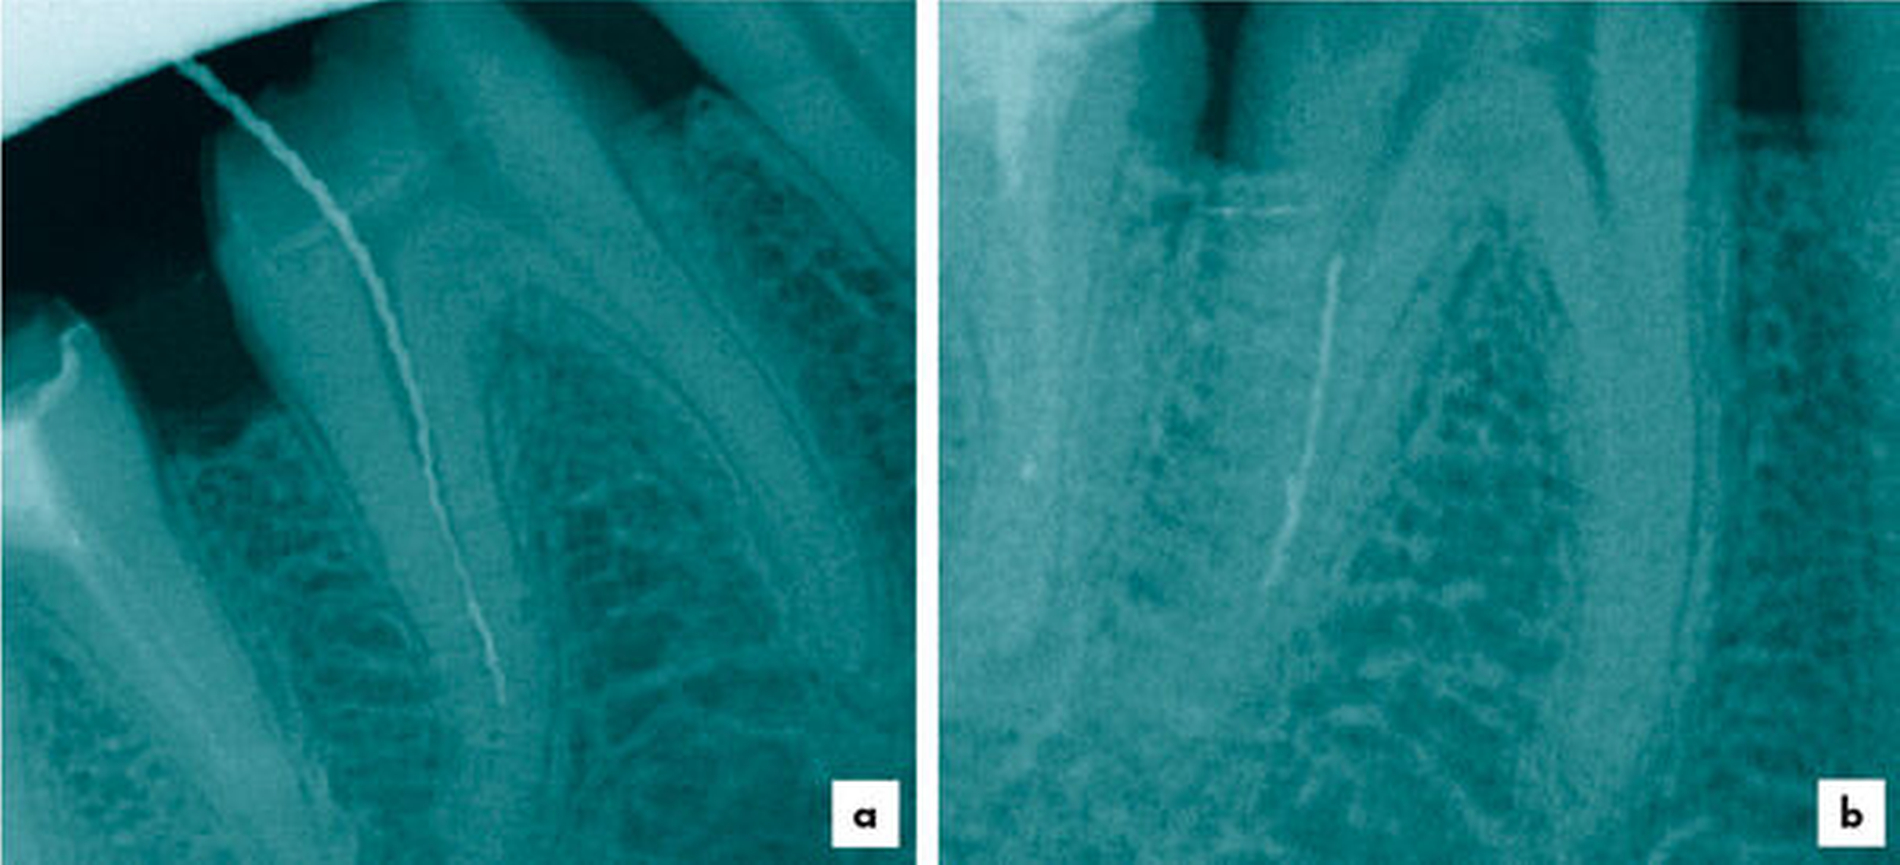

Es existieren verschiedene Techniken und Methoden, mit denen Instrumente entfernt werden können [Madarati, 2013]. Im Speziellen soll hier auf die Entfernung mittels einer selbst herstellbaren Tube-Dorn-Apparatur eingegangen werden. Diese Technik ist bei langen Fragmenten indiziert, wenn der koronale Anteil des zu entfernenden Instruments im koronalen oder im mittleren Wurzeldrittel lokalisiert ist (Abbildung 1). Der apikale Instrumentenanteil kann hierbei im mittleren oder im unteren Wurzeldrittel oder sogar über den Apex hinaus lokalisiert sein [Arnold, 2013].

Die Voraussetzung zur Anwendung dieser Technik ist, dass das Instrument im koronalen Anteil 2 bis 3 mm geradlinig freigelegt wird, damit eine kleine, seitlich aufpräparierte Kanüle das Fragment umfassen kann. Das koronale Fragmentende ragt aus der lateralen Öffnung der Kanüle idealerweise hinaus (Abbildung 2). Im Anschluss wird ein Stempel vorsichtig nach apikal bewegt und das Fragment in der Kanüle mechanisch an drei Punkten verkeilt.

Ein 64-jähriger Patient wurde mit zwei frakturierten Hedströmfeilen in der distalen Wurzel von Zahn 46 überwiesen. Der Vorbehandler hatte versucht, das erste Fragment mit einer weiteren Hedströmfeile schraubend zu entfernen, jedoch frakturierte auch diese unter der hohen Torsionsbelastung (Abbildung 3).